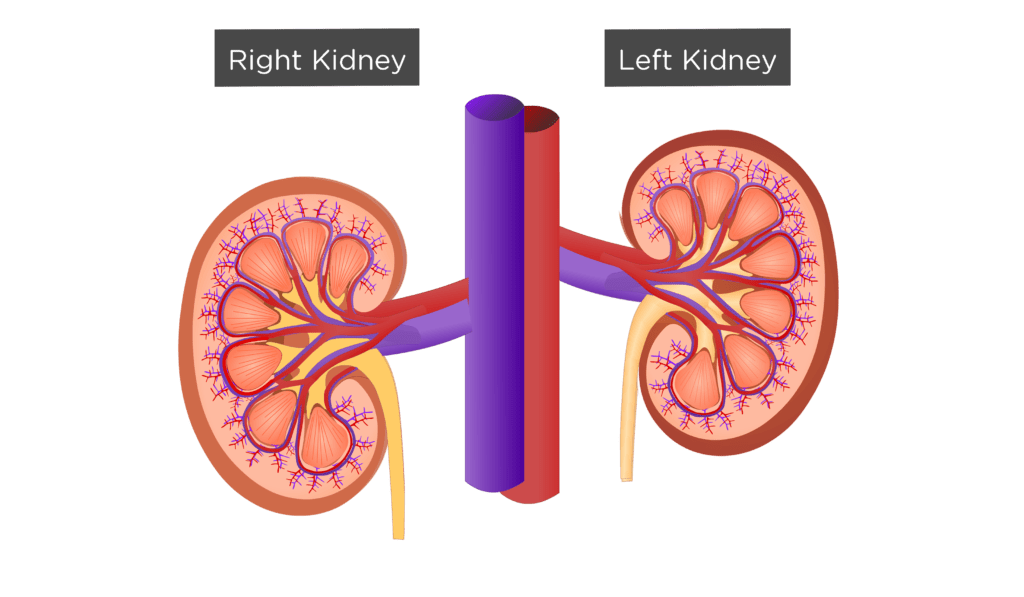

Строение почек человека: Фото и описание